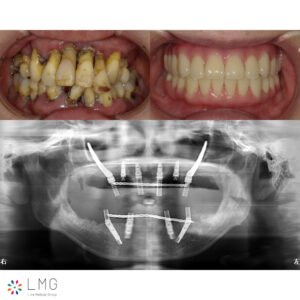

下顎オールオンフォー、上顎ザイゴマインプラント 「ザイゴマインプラント治療」を行われた患者さまのビフォーアフターをご紹介します。 ※ご紹介している症例は、あくまでも患者様固有の症例ですので、実際には患者様によって治療期間 […]